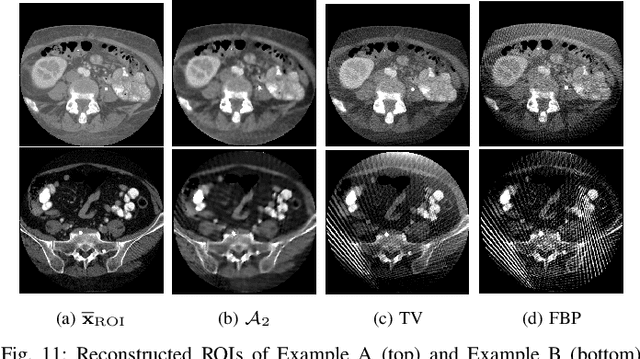

Abstract:This paper addresses the problem of image reconstruction for region-of-interest (ROI) computed tomography (CT). While model-based iterative methods can be used for such a problem, their practicability is often limited due to tedious parameterization and slow convergence. In addition, inadequate solutions can be obtained when the retained priors do not perfectly fit the solution space. Deep learning methods offer an alternative approach that is fast, leverages information from large data sets, and thus can reach high reconstruction quality. However, these methods usually rely on black boxes not accounting for the physics of the imaging system, and their lack of interpretability is often deplored. At the crossroads of both methods, unfolded deep learning techniques have been recently proposed. They incorporate the physics of the model and iterative optimization algorithms into a neural network design, leading to superior performance in various applications. This paper introduces a novel, unfolded deep learning approach called U-RDBFB designed for ROI CT reconstruction from limited data. Few-view truncated data are efficiently handled thanks to a robust non-convex data fidelity function combined with sparsity-inducing regularization functions. Iterations of a block dual forward-backward (DBFB) algorithm, embedded in an iterative reweighted scheme, are then unrolled over a neural network architecture, allowing the learning of various parameters in a supervised manner. Our experiments show an improvement over various state-of-the-art methods, including model-based iterative schemes, deep learning architectures, and deep unfolding methods.